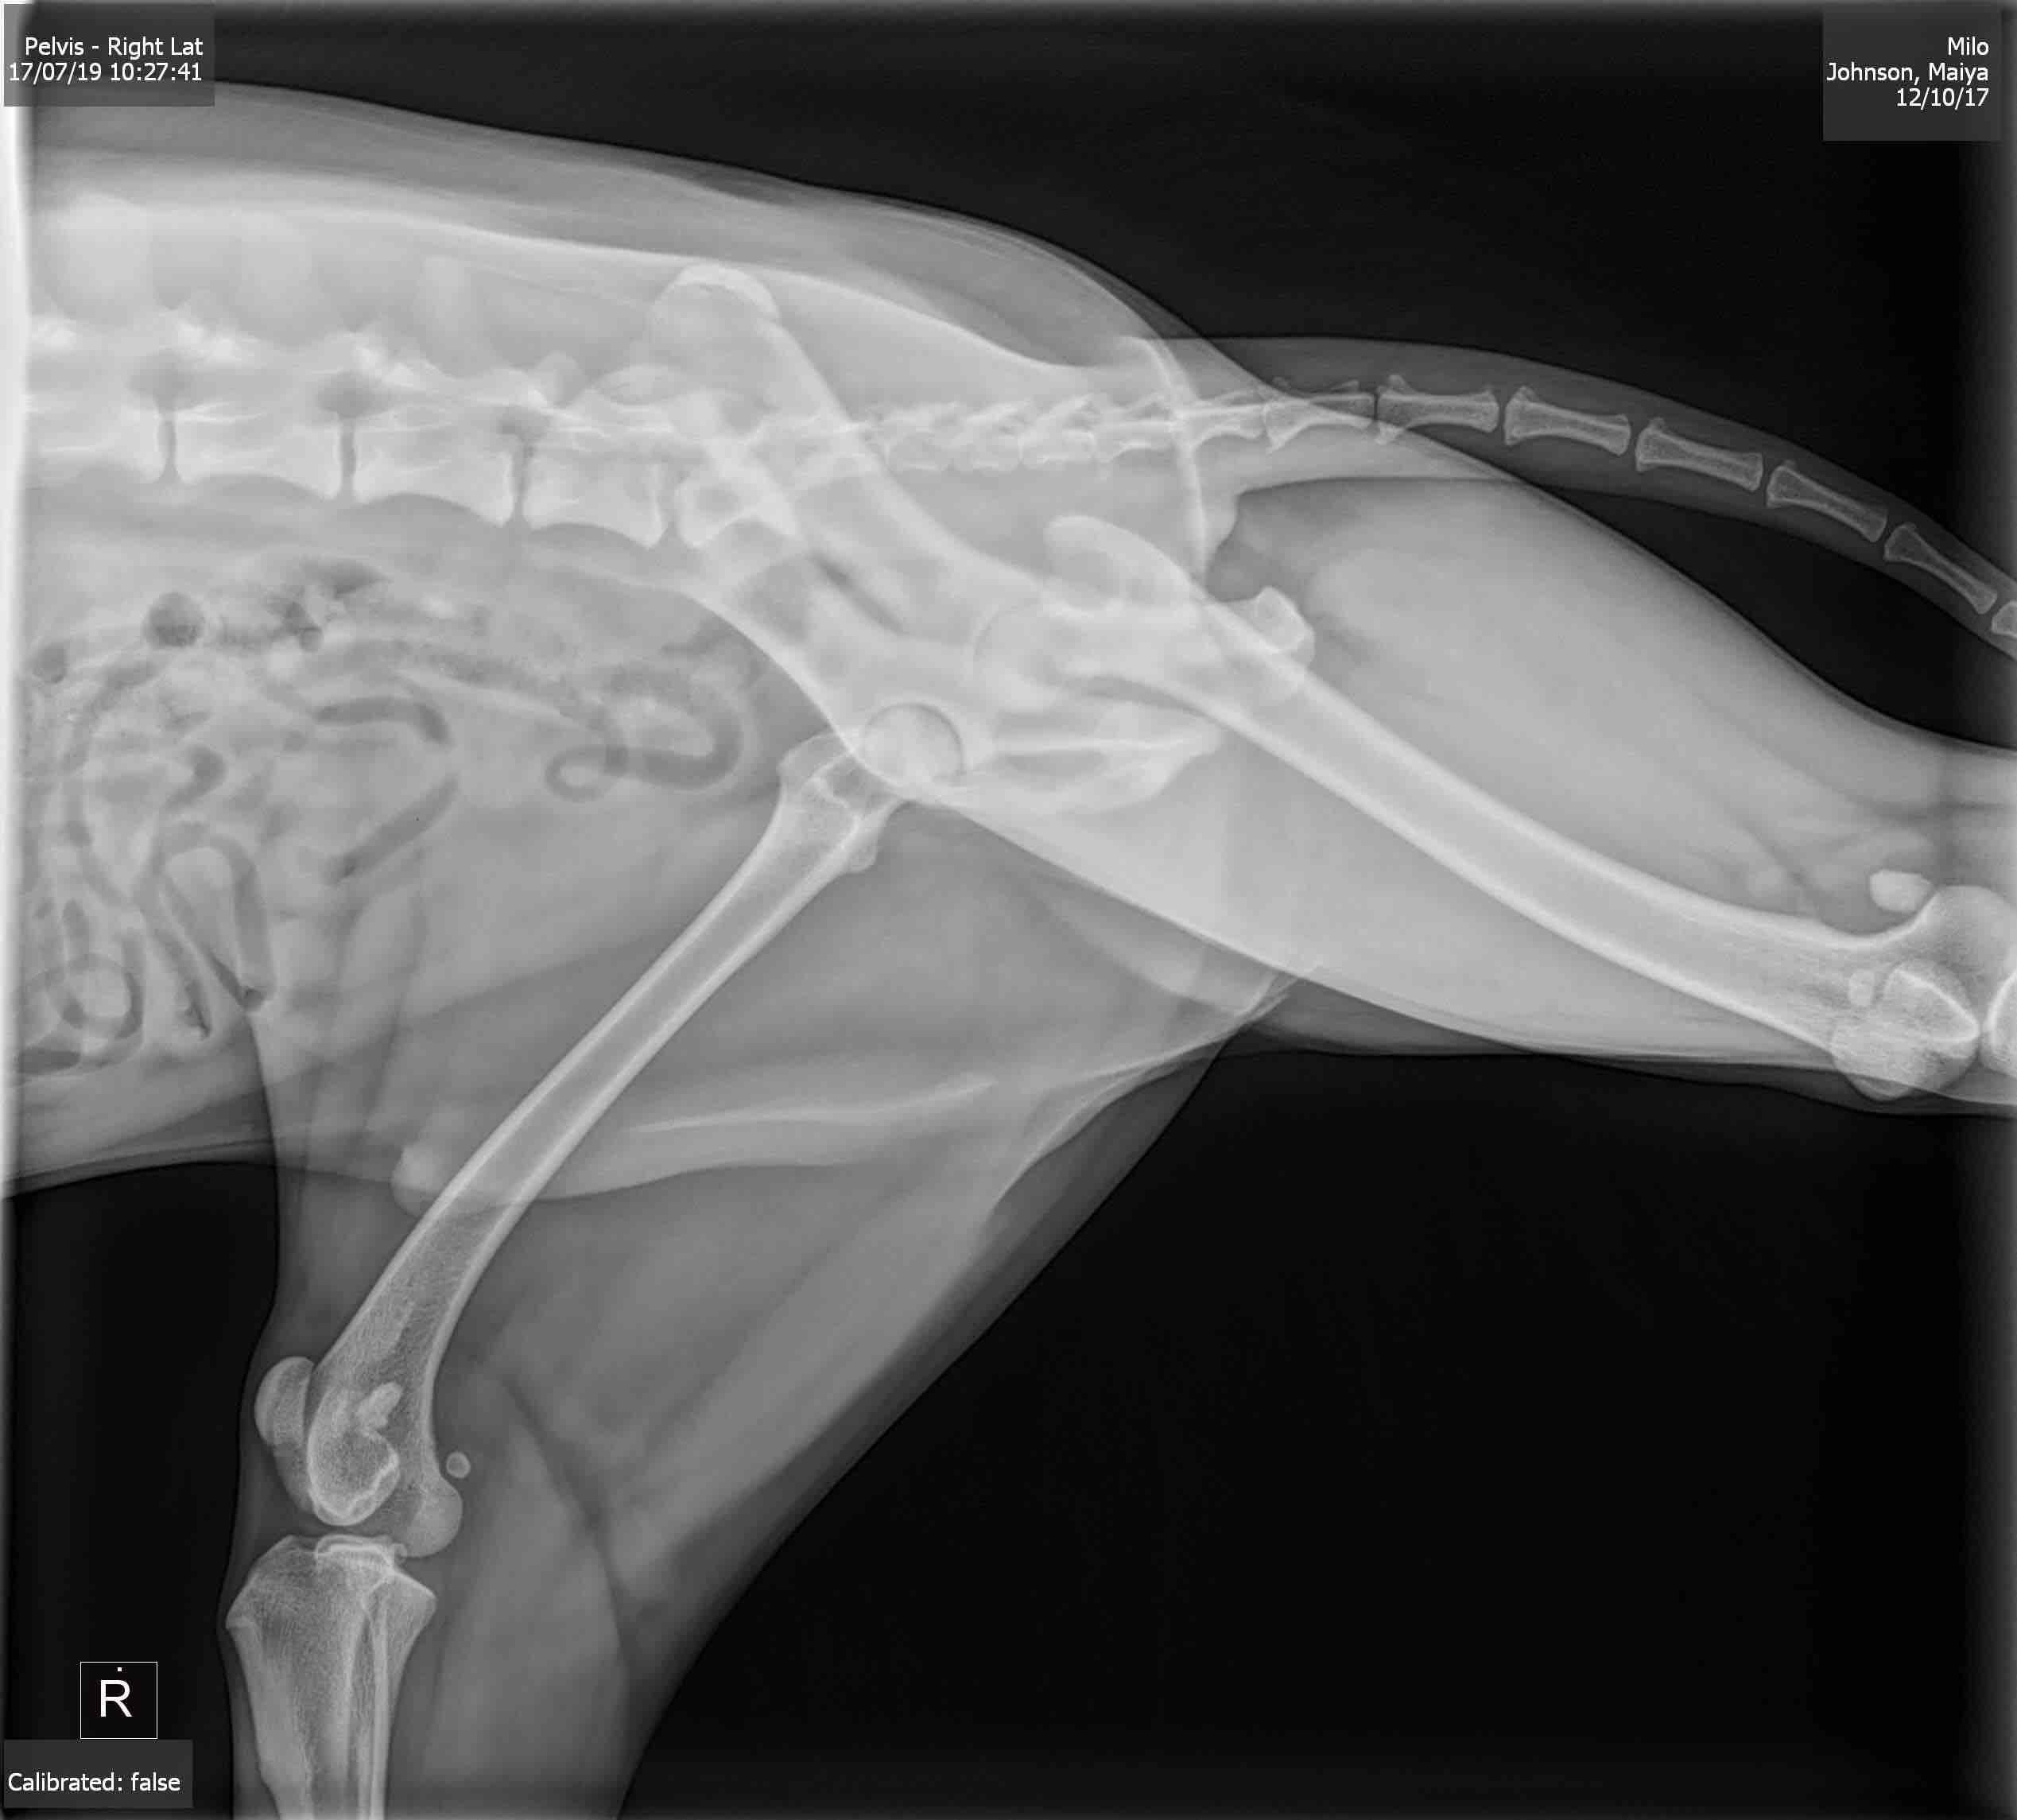

Pet's info: Dog | Australian Shepherd - miniature | Male | neutered | 1 year and 9 months old | 33 lbs

My pup recently had these rads taken, I’m looking to see what someone else sees in them and some prognosis. We’re trying to make educated next steps for the little guy. He’s so young.

Looks like mild hip dysplasia of the left hip. There also seems to be narrowing if the medial joint space in the right knee but this could be due to positioning. It would be easier to give you advice if you could give us more information about Milo’s clinical signs and what diagnosis your vet gave.